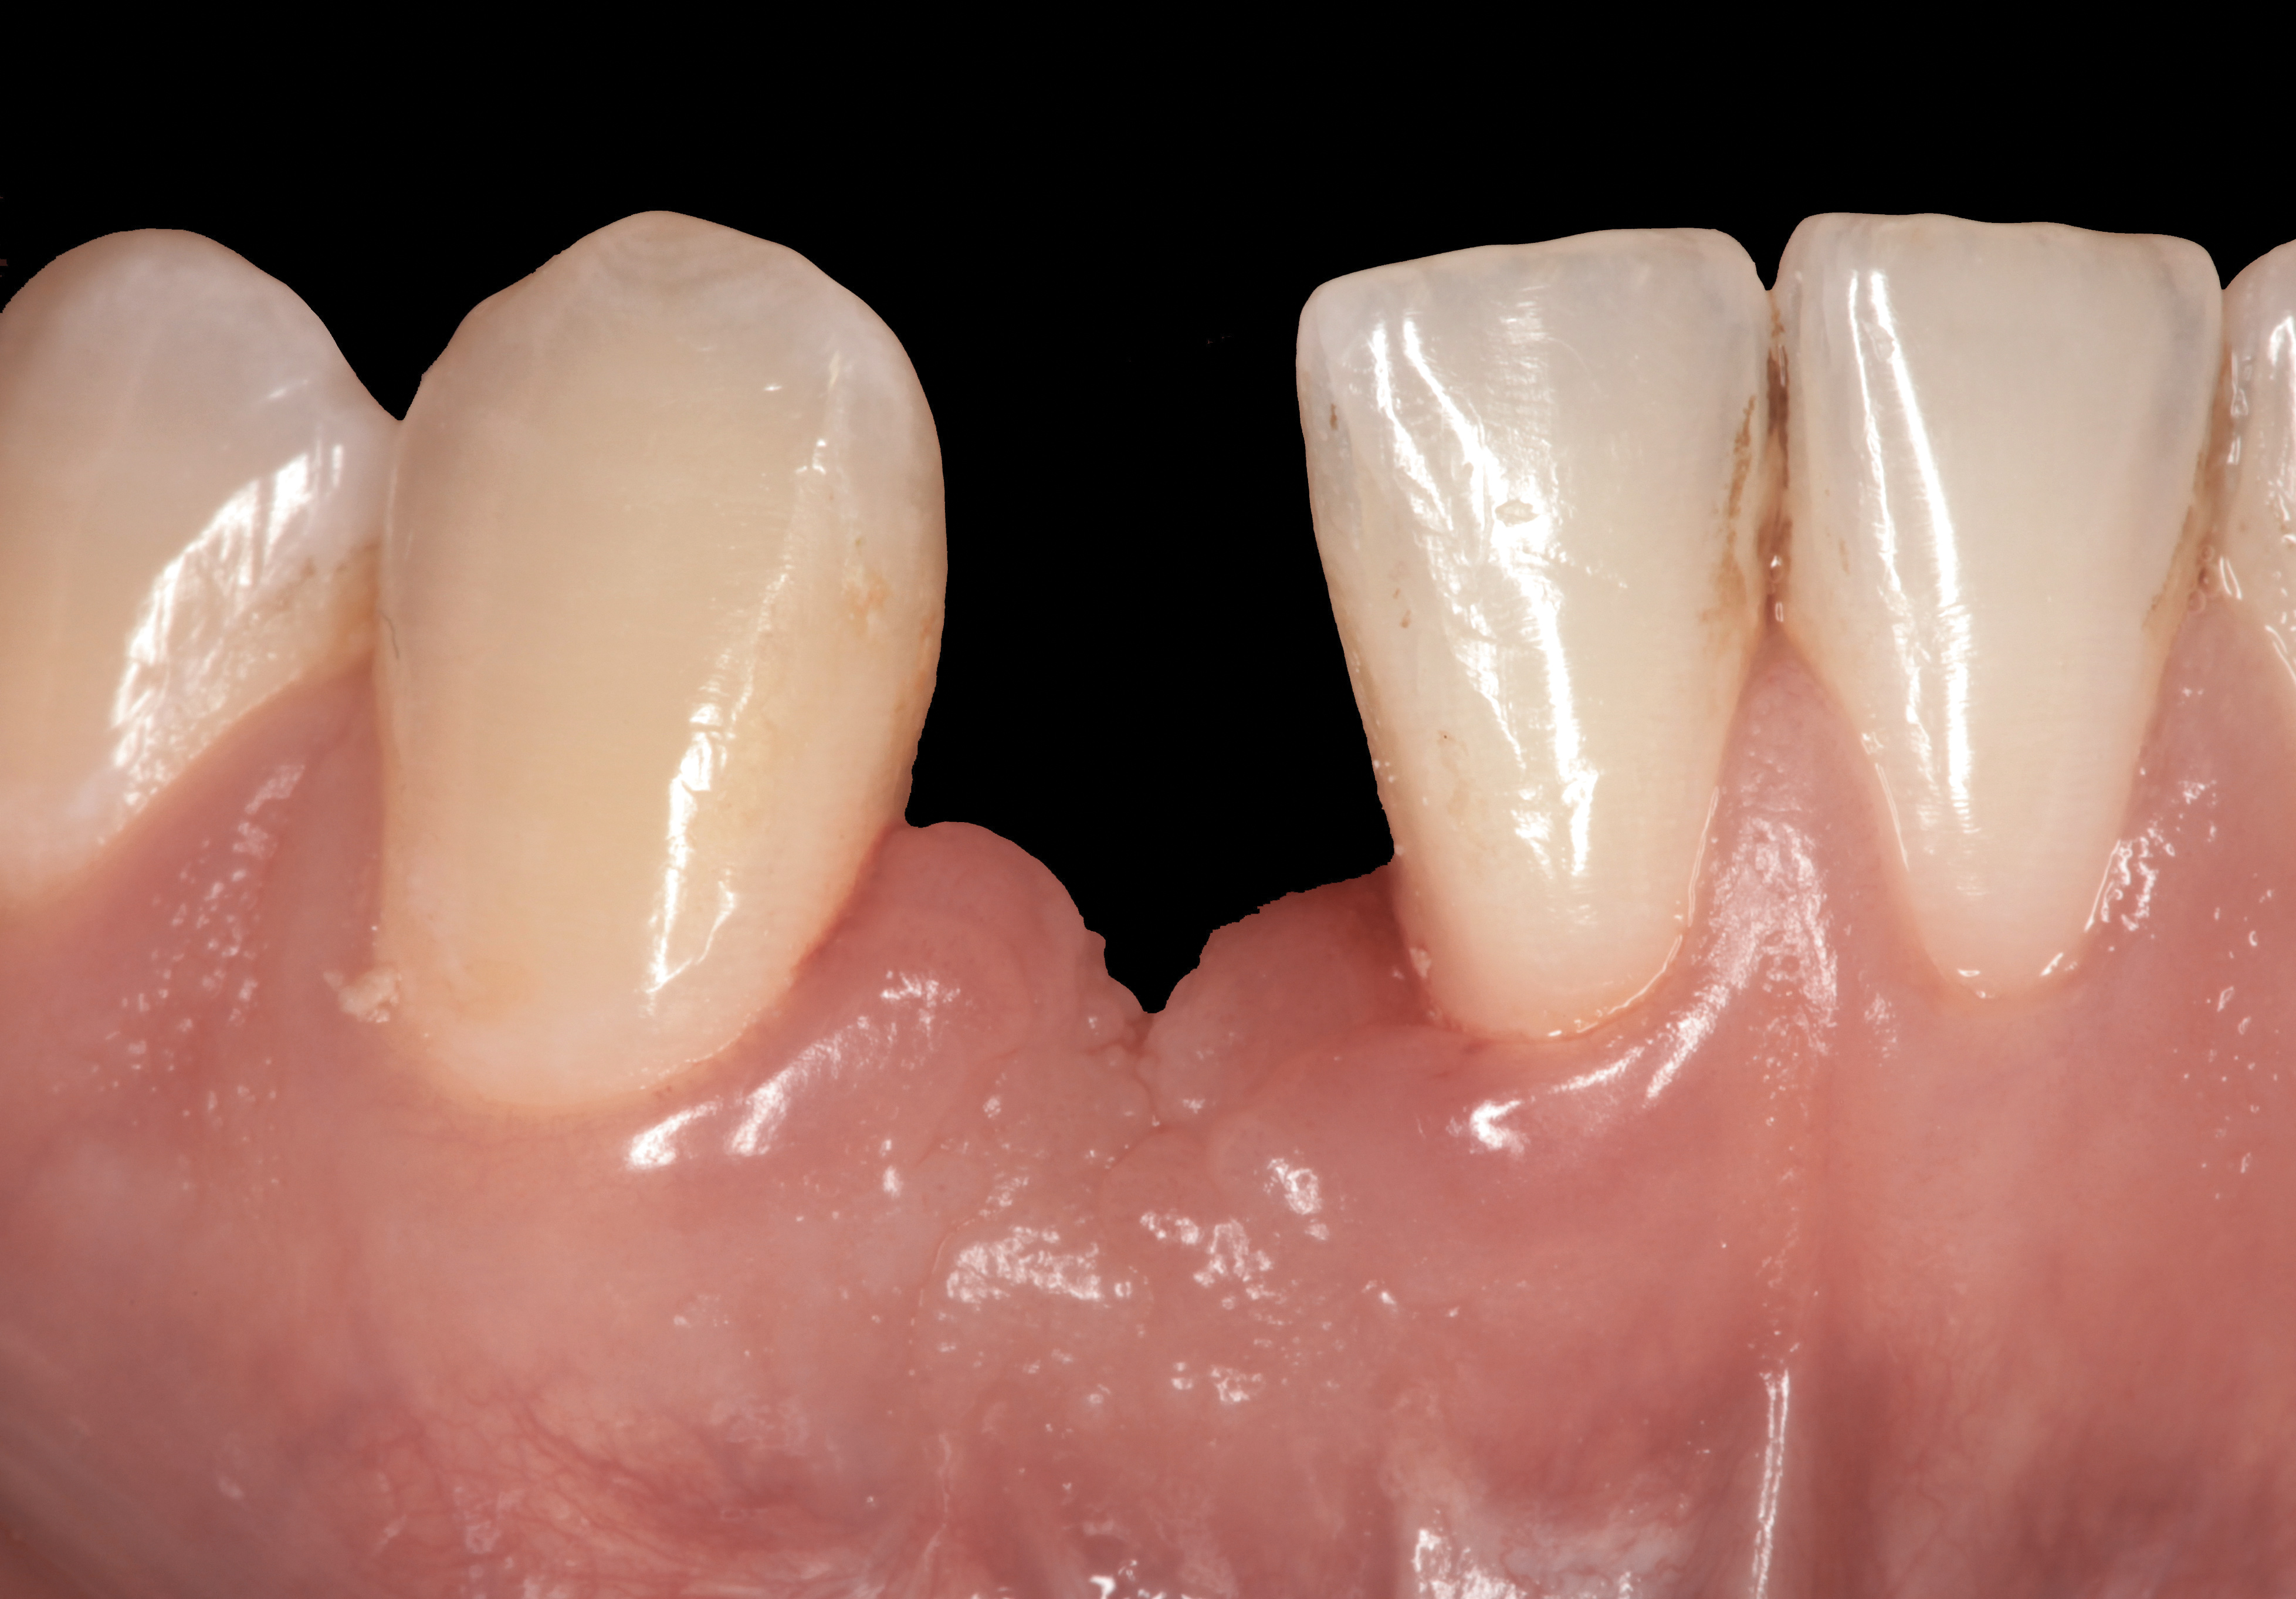

Case Scenario No. 2

Problem: The implant is placed too facially, and there is significant labial gingival recession, contour change, and mucosal discoloration around the implant, abutment, and crown (Figure 3 and Figure 4). The implant attachment apparatus is intact and healthy, but the patient has a thin periodontal phenotype.

Solution: (1) Decoronate the implant with a sterile cover screw. (2) Place a tooth-supported fixed transitional provisional restoration such as a temporary resin-bonded–retained “Maryland-type” bridge and allow the mucosal tissues to “creep” over the cover screw for a few weeks. (3) Place a subepithelial connective tissue graft to augment the soft tissues both horizontally and vertically. (4) Two months later, perform a second-stage implant uncovering and place a flat-profiled healing abutment. (5) After a few weeks of soft-tissue healing, manage the subgingival restorative contours of the provisional and definitive restoration.

The following case report provides an example of this case scenario: A 28-year-old white female patient presented with her maxillary right lateral incisor significantly longer than the contralateral tooth following restoration of an existing crown that was 10 years old (Figure 3). The patient was dissatisfied with the esthetic appearance of the restoration due to the increased length, recession of the gingival tissues, and discoloration of the surrounding mucosa (Figure 4). Similar to case scenario No. 1, the first step in treatment was to decoronate the healthy implant by placing a flat surgical cover screw and employing a provisional resin-bonded-retained (RBR) prosthesis as a transitional fixed restoration (Figure 5 and Figure 6). The gingival augmentation in situ was allowed to take place for 2 to 3 weeks and was evaluated after that time (Figure 7).

Fig 3. A patient presented with a high smile line and midfacial recession of the maxillary right lateral incisor as evidenced by the increased tooth length compared with the contralateral lateral incisor.

Figure 3

Fig 4. Intraoral view of tooth No. 7 with the gingival zenith more apical than the adjacent central incisor and canine tooth.

Figure 4